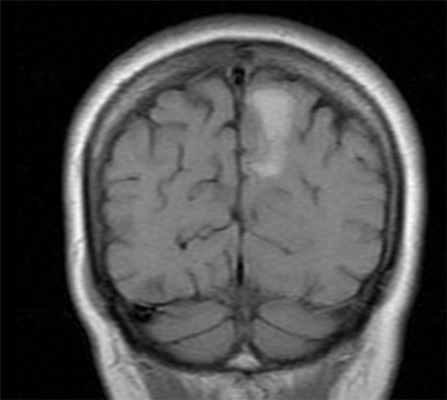

МРТ головного мозга. Т1-взвешенная корональная МРТ. Смешанный ишемический инсульт. Ранняя подострая стадия.

Субдуральная гематома обычно возникает вследствие разрыва вен. Причины субдуральной гематомы – травма, антикоагулянтная терапия, резкая декомпрессия при шунтировании желудочков по поводу гидроцефалии. Очень редко встречаются субдуральные гематомы при разрыве аневризм и АВМ. Клинические проявления связаны смасс-эффектом. Частота субдуральных гематом составляет около 1 случая на 10 тысяч населения. Располагаются субдуральные гематомы по конвекситальной поверхности, изредка, вдоль межполушарной щели и намёта, в области задней черепной ямки. Может быть сочетание субдуральной гематомы с кровоизлиянием в соседние участки мозга. прогноз в этих случаях неблагоприятный. Отображение гематомы на КТ и МРТ зависит от их давности. Субдуральные гематомы имеют форму серпа.

МРТ головного мозга. Аксиальная Т2-взвешенная МРТ. Подострая субдуральная гематома.